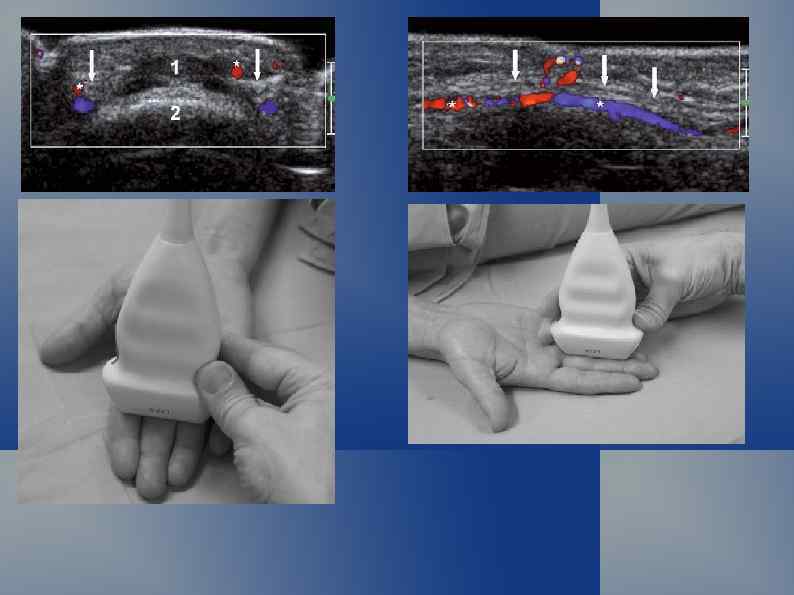

Артерио-венозная мальформация

Венозная мальформация. Эктазия вены с флеболитам.

Артерио-венозные мальформации и гемангиомы мягких тканей Первые упоминания, касающиеся артериовенозных соустий сосудов конечностей, относятся к XVIII в. , когда в 1737 г. появились публикации В. Hunter, описавшего артериовенозные фистулы. Одной из первых фундаментальных работ по врожденной сосудистой патологии является монография Trelat и Movod (1869), в которой авторы пришли к выводу, что заболевание, характеризующееся гипертрофией конечностей, варикозным расширением подкожных вен и капилляров, возникает вследствие врожденного нарушения развития сосудов.